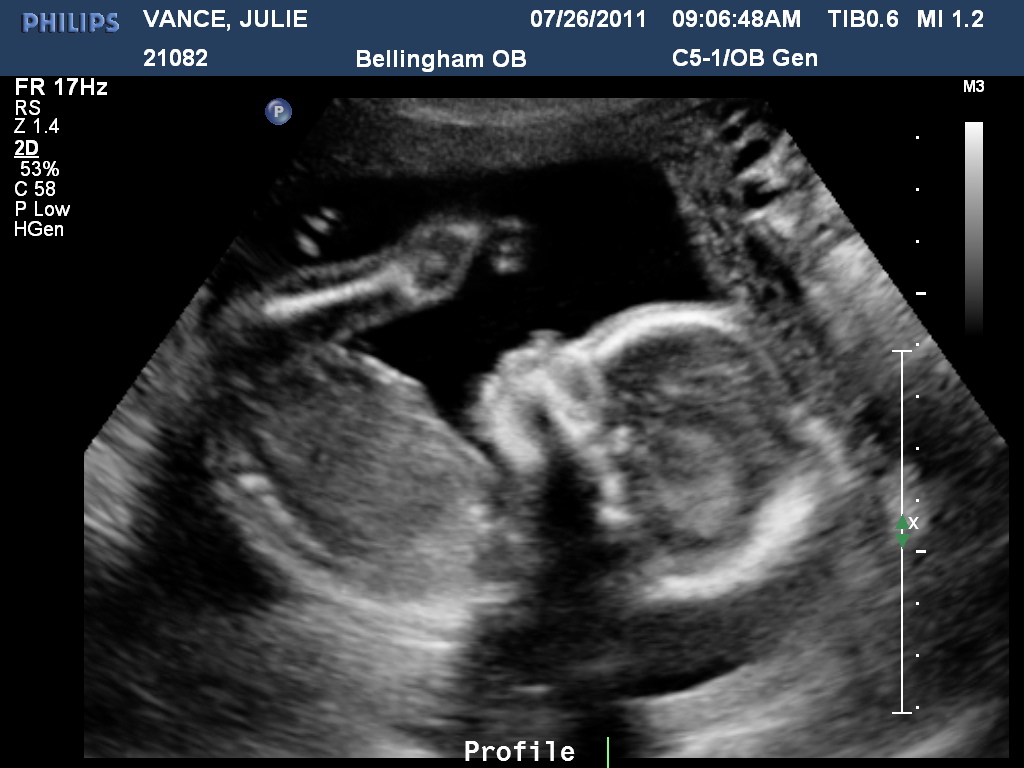

>> July 26, 2011

Today we had our 20 week ultrasound for baby #2. When I was pregnant with Carter, I had no doubt he was a boy. But, this baby I wasn't too sure. I ended up thinking boy because the pregnancies have been so similiar - no nausea or vomiting, feeling great and having the exact same cravings!

So, it came as quite a surprise when we found out our little GIRL will be arriving in December. I cried, Matt grinned from ear to ear and we are both already so in love. It'll be a whole new world with a girl. I have learned to love fire trucks, loud animal sounds, choo choo trains and dirt but will now experience tutus, pigtails and tea parties! Oh my goodness, what an adventure we have waiting for us! Our little girl was quite stubborn during the ultrasound. We are hoping this isn't a reflection of her personality! She just wanted to sit very, very low and although she'd move quite a bit, it was never in the direction she needed to go for some good pictures!

Waving hi to mom and dad!

Cute little hand.

And adorable toes!

And proof she's a girl!!!

Welcome baby girl vance!!! We love you!